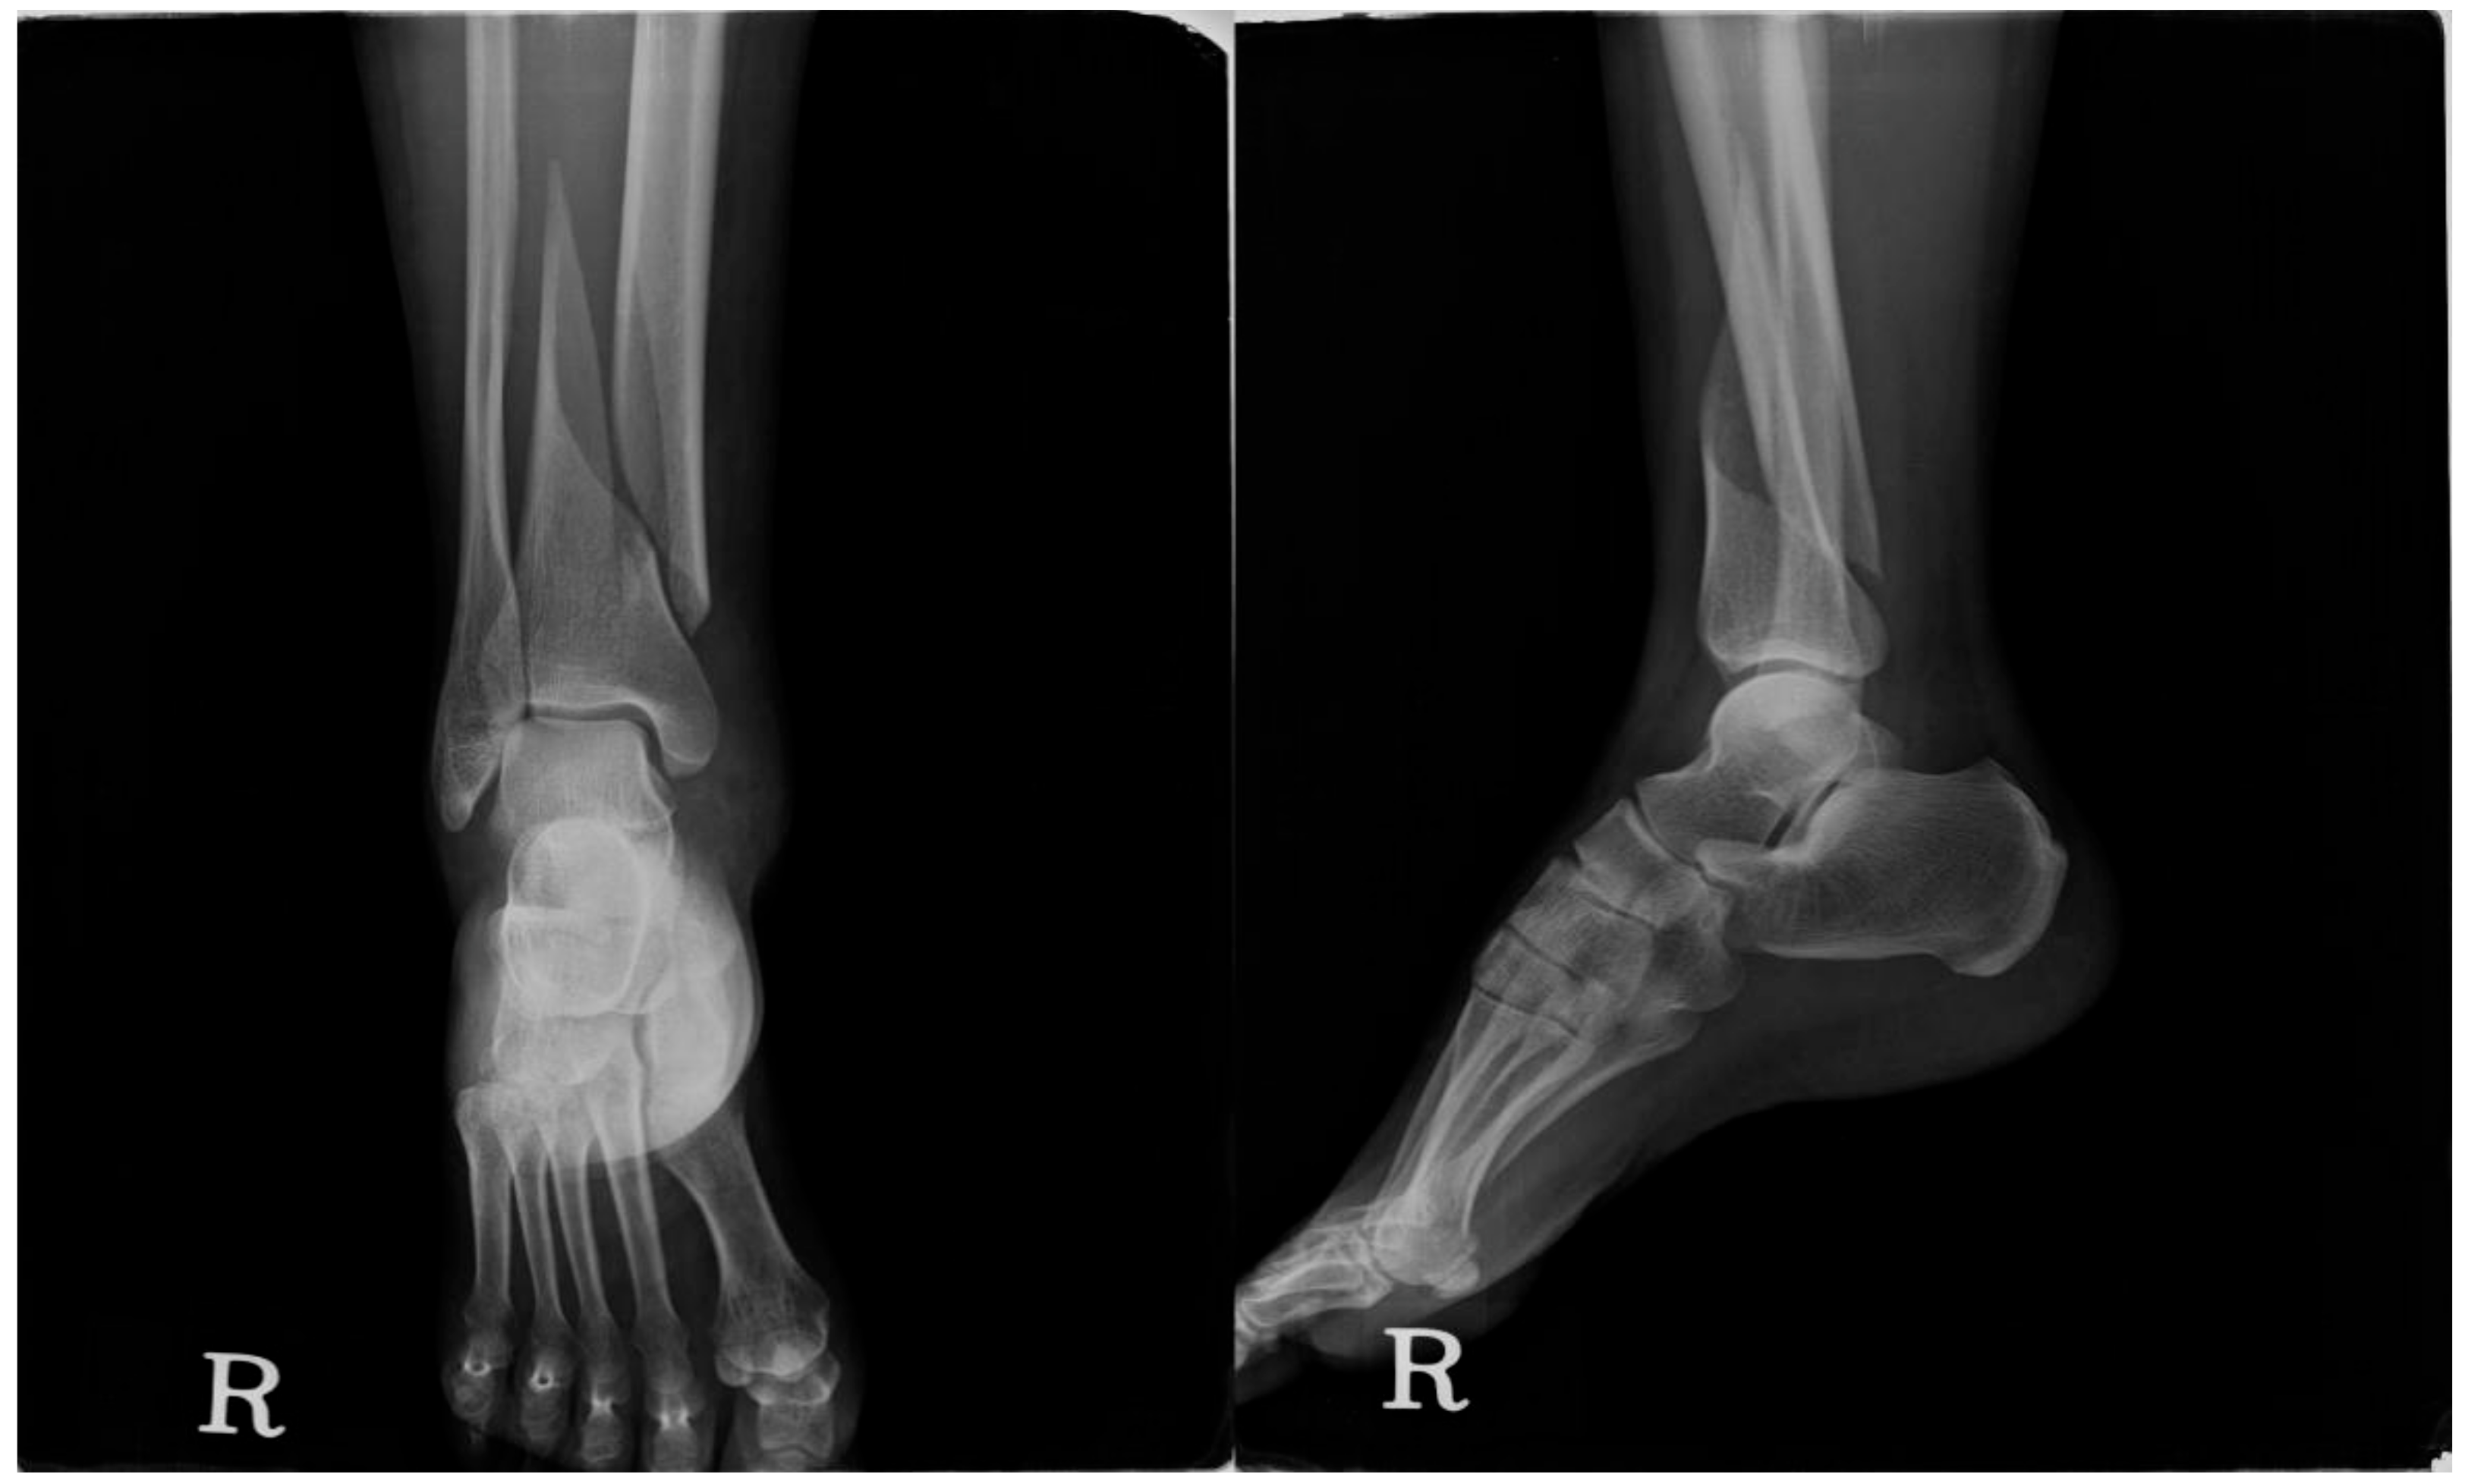

Four hours later, I was sitting in the ER with a cast on my wrist.

Distal radius fracture. Clean break.

The doctor came in with my X-rays.

But he also had another image pulled up on his screen.

"Mrs. Martinez, I want to show you something."

He pointed to the X-ray of my wrist.

"See how the bone looks here? The density. The structure."

I nodded, not understanding.

"This shouldn't have broken from a simple fall off a curb. Not at your age. Not with this kind of impact."